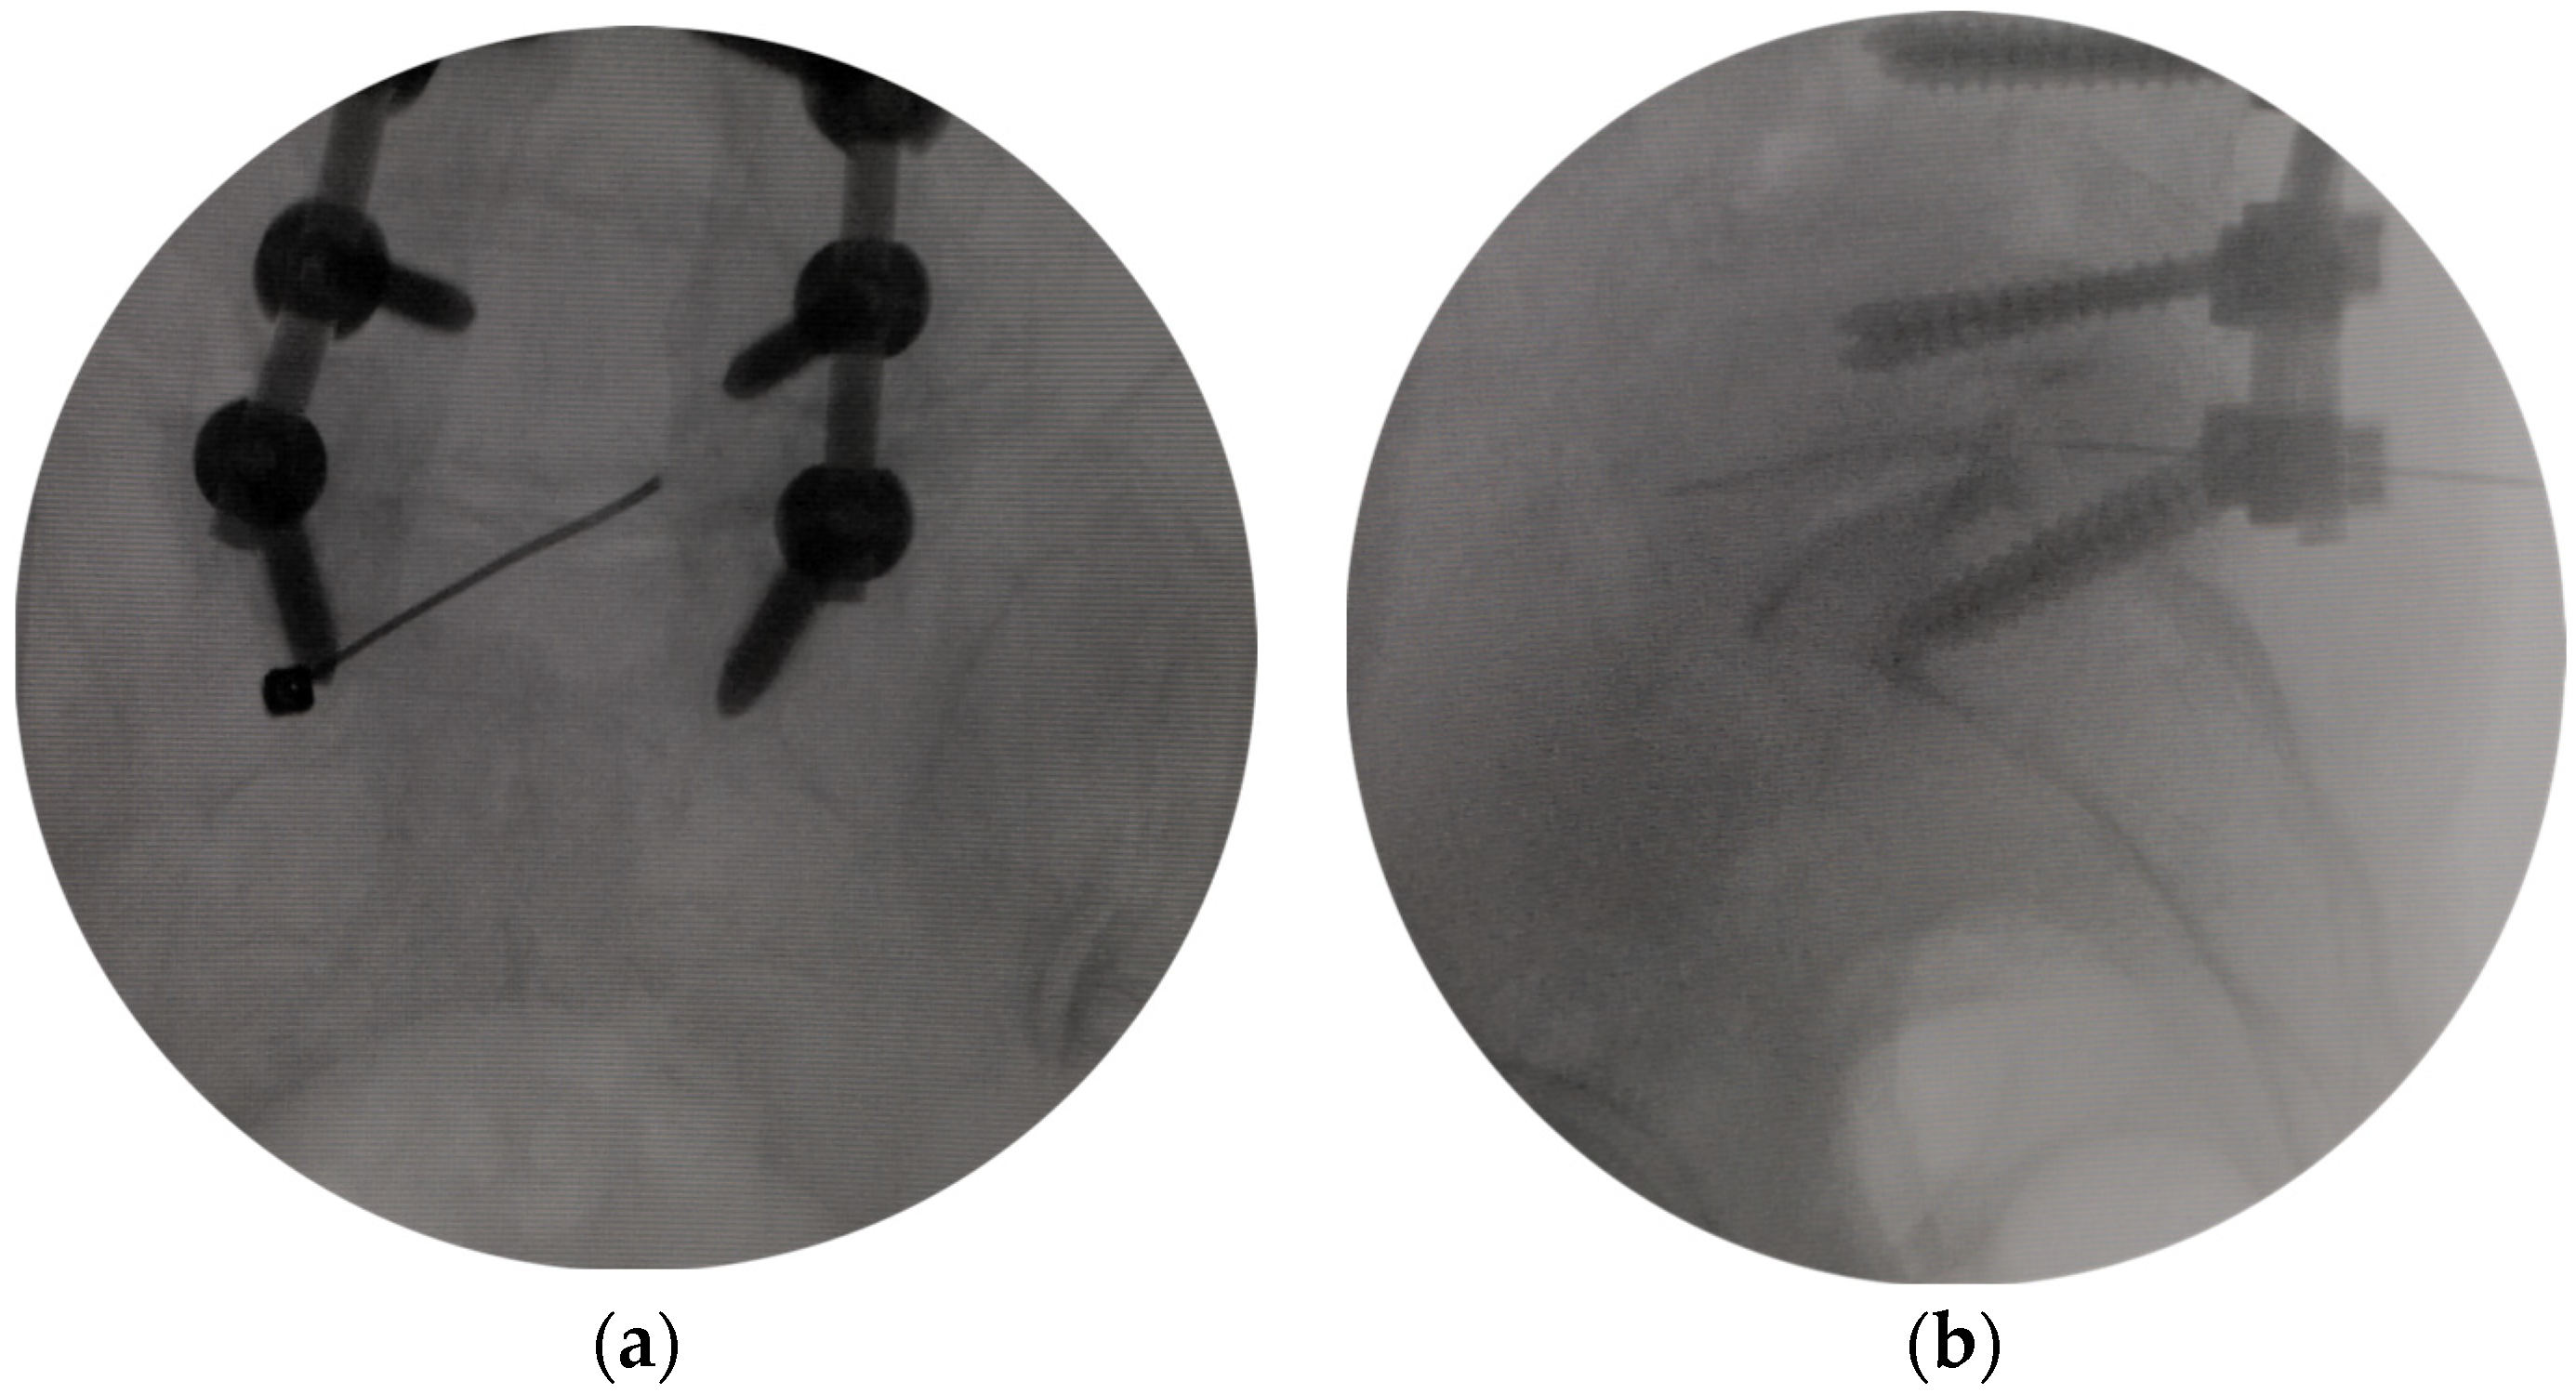

2.3. Surgical Procedures

- The modified interlaminar approach we used can show an almost parallel trajectory to the L5 nerve root in the foramen and provide excellent visualization of the nerve root all along its course without the need for significant retraction. This technique was called “no touch decompression” [36], as FS can be treated without more retraction of DRG compared with that via transforaminal approach, especially in complicated cases and L5-S1 cases with anatomical limitations [37].

- Dissecting scar tissue from bone rather than nerve tissue is an effective method to reduce the risk of dural tear [42]. Bone tissue at the lateral and dorsal sides of the nerve structure was treated after the tip of the trephine, and anatomical landmarks were identified in X-ray view. The unscarred virgin tissue can be easily viewed and entered by endoscopic. Therefore, the operation can be safely performed without excessive retraction of the dura, nerve root, and DRG, which may be tethered at the foramen, and dissection of the scar tissues surrounding the nerve structure.

- The entry direction of the instrument is not toward the nerve root and dural sac. The operation in the spinal canal is far from the dural sac and nerve root, and the operation in the intervertebral foramen is parallel to the nerve root. It reduces the risk of dural tear and neural injury.